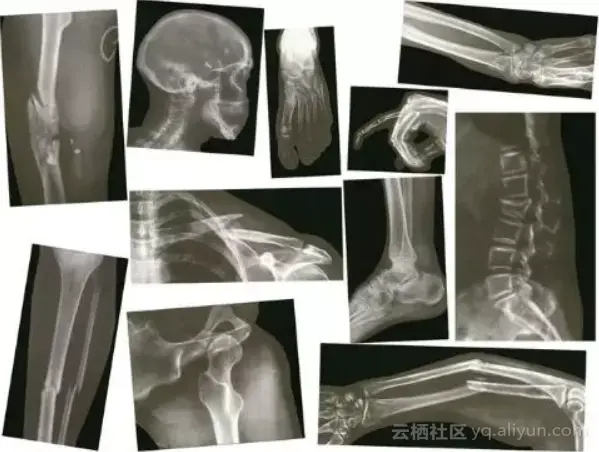

但在医学数据中,许多问题其实很简单。因为医学图像的变化是很小的。解剖学、角度、光线、距离和背景都很稳定。为了说明这一点,让我们看一个来自CXR14的简单示例。在数据集中的普通胸部x光中,有一些是旋转的(这在标签中没有被识别,所以我们不知道是哪一个)。它们可以旋转90度左右,或180度的上下颠倒。

c058087825a6c39614814097ff449ce3c96979d0

图3:旋转和垂直的胸部x光的区别真的非常简单

答案是肯定的。从视觉上看,异常的研究与正常的研究完全不同。你可以使用一个简单的视觉规则,比如“肩膀应该高于心脏”,你会在所有的样例上得到验证。鉴于解剖学是非常稳定的,而且所有人都有肩膀和心脏,这应该是一个可学习的卷积神经网络规则。